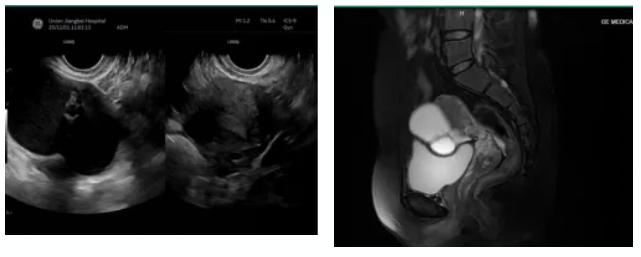

“医生,我肚子上到底会留几个洞啊?”躺在手术台上,即将接受麻醉的杨女士,还在反复确认这个问题。这位40岁的患者,因月经紊乱于2026年1月13日在我院妇科门诊就诊时发现右侧附件区有一个7.6×5.0cm的囊肿。当得知需要手术时,她最担心的不是手术本身,而是像同事那样,在肚子上留下3-4个显眼的疤痕。

我院妇科陈静主任接诊后,为她推荐了单孔腹腔镜技术—这是一种经脐孔自然通道进入腹腔的微创术式,仅需一个孔道即可完成手术。主管医师黄美兰与黄英副主任,在术前为她做了充分评估:肿瘤标志物全阴性、盆腔磁共振提示良性可能大、包块活动度良好,完全符合单孔腹腔镜的手术指征。